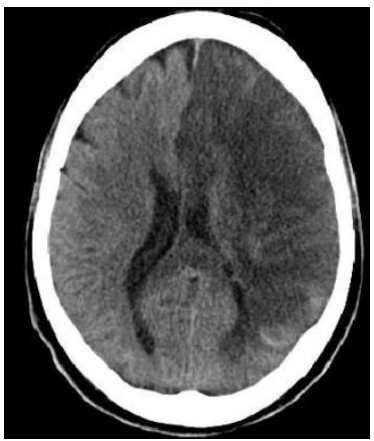

Tomografia computadorizada de crânio sem contraste, com

hipodensidade fronto-parieto-temporal volumosa à esquerda,

apagamento de sulcos e desvio contralateral da linha média.